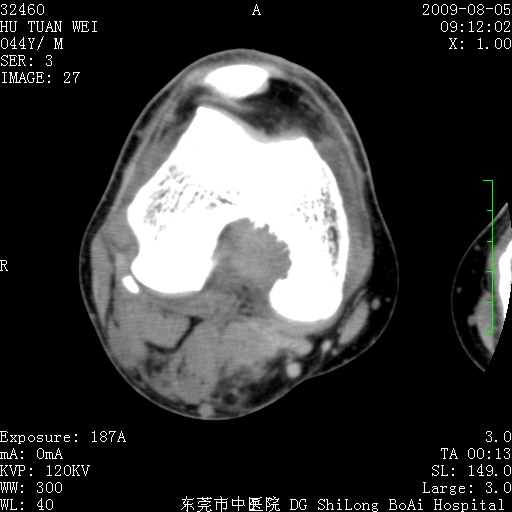

中年男性,膝韧带损伤术前检查!其他病史不清粗,不是我接手病人、且出院了!

1、股骨下段囊状膨胀性病变,边缘硬化明显,内多个残留骨棘呈多房型改变,囊腔密度较高无钙化,膝关节滑膜囊增厚,密度增高,关节腔少量积液。考虑:邻关节囊肿、退变性囊肿(软骨下囊肿)、着色性绒毛结节性滑膜炎、abc、骨巨、良性纤维组织细胞瘤等鉴。虽然年龄偏大,部位于骨端,但有外伤史,本人还是倾向于动脉瘤样骨囊肿(abc)可能性大。邻关节囊肿及软骨下囊肿次之考虑。

2、胫骨髁间棘撕脱骨折,交叉韧带损伤可能;

3、关节退行性改变。

病理结果:色素沉着绒毛结节性滑膜炎

感谢反馈病理结果!本病为慢性关节病变。以关节滑膜高度增生、绒毛结节形成伴含铁血黄素趁着为特点。病因:有炎症、肿瘤、外伤关节出血、代谢障碍、变态反应及感染等学说。增强扫描呈关节腔内单个或多个强化的软组织结节影或滑膜不规则增厚伴关节积液为本病的特征性表现。